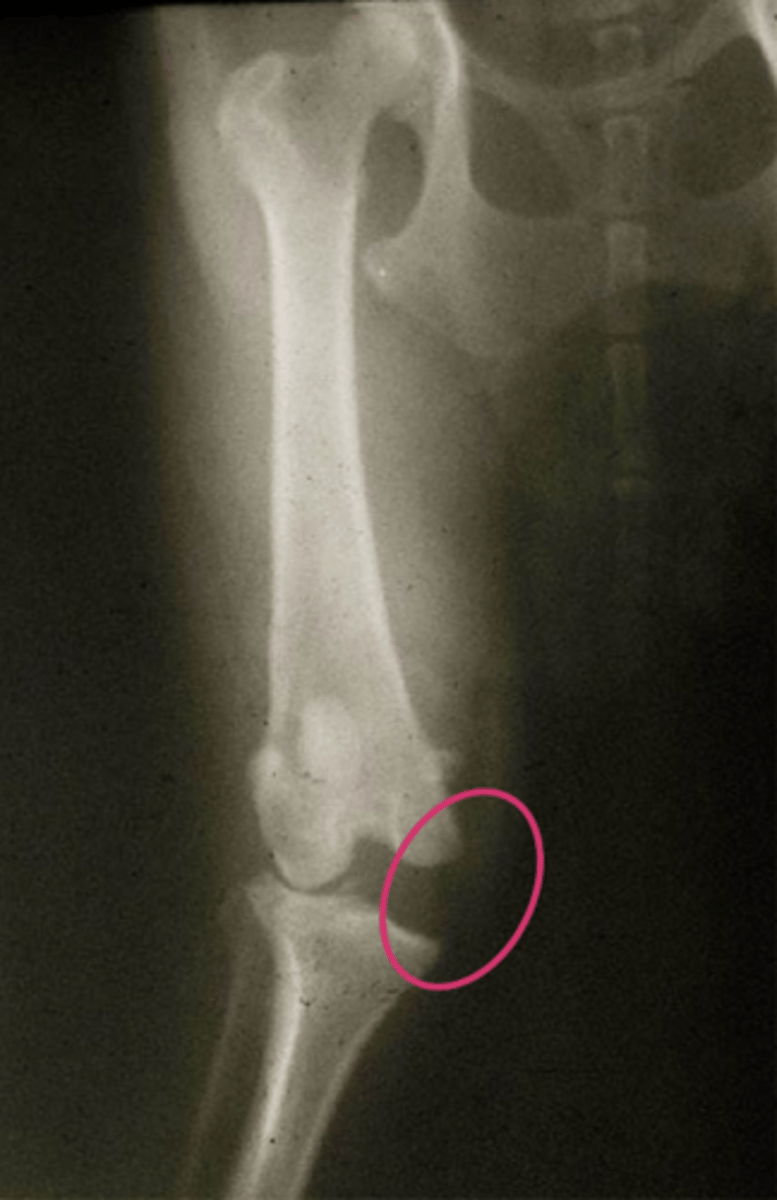

CaCL rupture w/ medial collateral lig. tear

what is shown here...